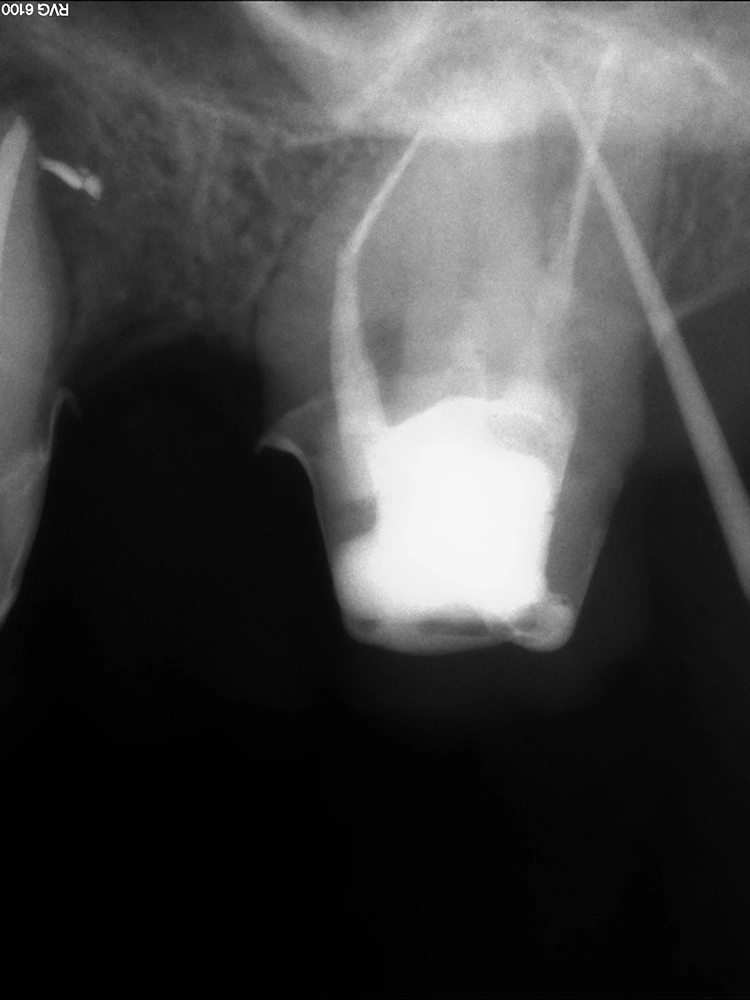

Diagnostische Grundlage

Die diagnostische Grundlage für eine sichere Lagebestimmung und Abschätzung der Zugänglichkeit des zu entfernenden Instrumentenfragmentes stellt eine zweidimensionale intraorale Röntgenaufnahme (Zahnfilm) dar, die bei Bedarf durch eine 2. Aufnahme aus einer alternativen Projektionsrichtung ergänzt werden kann. Im Ausnahmefall ist eine dreidimensionale Darstellung (DVT) hilfreich.

Deutlicher zeitlicher Mehraufwand liegt häufig in prozessualen Fehlern, wie bspw. übermäßigem Zahnhartsubstanzabtrag, begründet. Dieser kann zu Kanalverlagerungen und -perforationen führen (Abb. 3a und b), die ein erhöhtes Risiko für anschließende Wurzellängsfrakturen sowie den Verlust des Zahnes darstellen können [12].